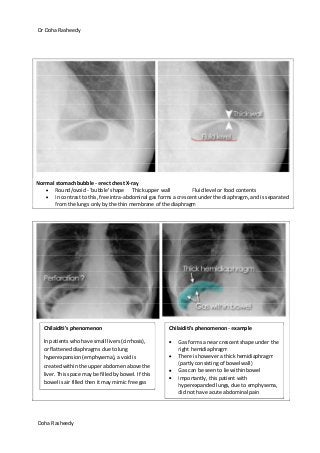

Normal stomach bubble - erect chest X-ray

Round/ovoid - 'bubble' shape Thick upper wall Fluid level or food contents

In contrast to this, free intra-abdominal gas forms a crescent under the diaphragm, and is separated

from the lungs only by the thin membrane of the diaphragm

Chilaiditi's phenomenon

In patients who have small livers (cirrhosis),

or flattened diaphragms due to lung

hyperexpansion (emphysema), a void is

created within the upper abdomen above the

liver. This space may be filled by bowel. If this

bowel is air filled then it may mimic free gas

Chilaiditi's phenomenon - example

Gas forms a near crescent shape under the

right hemidiaphragm

There is however a thick hemidiaphragm

(partly consisting of bowel wall)

Gas can be seen to lie within bowel

Importantly, this patient with

hyperexpanded lungs, due to emphysema,

did not have acute abdominal pain